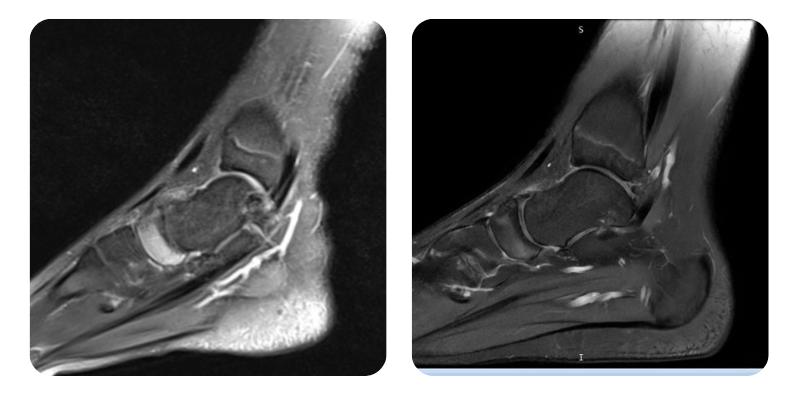

Before

After

Anamnesis: The patient presents with aseptic osteonecrosis of the navicular bone in the left foot. He suffered a sprain 7 months ago, which temporarily improved. For the past month, the foot pain has returned. MRI confirmed the diagnosis. Pain intensity was 6–7/10, especially in the morning. No chronic medication, no prior medical history.

Evolution: At follow-up, the patient reports that the pain has almost completely disappeared, now 1/10 compared to 6–7/10 initially. Mobility has improved. Control MRI shows an approximate 70% reduction in edema.